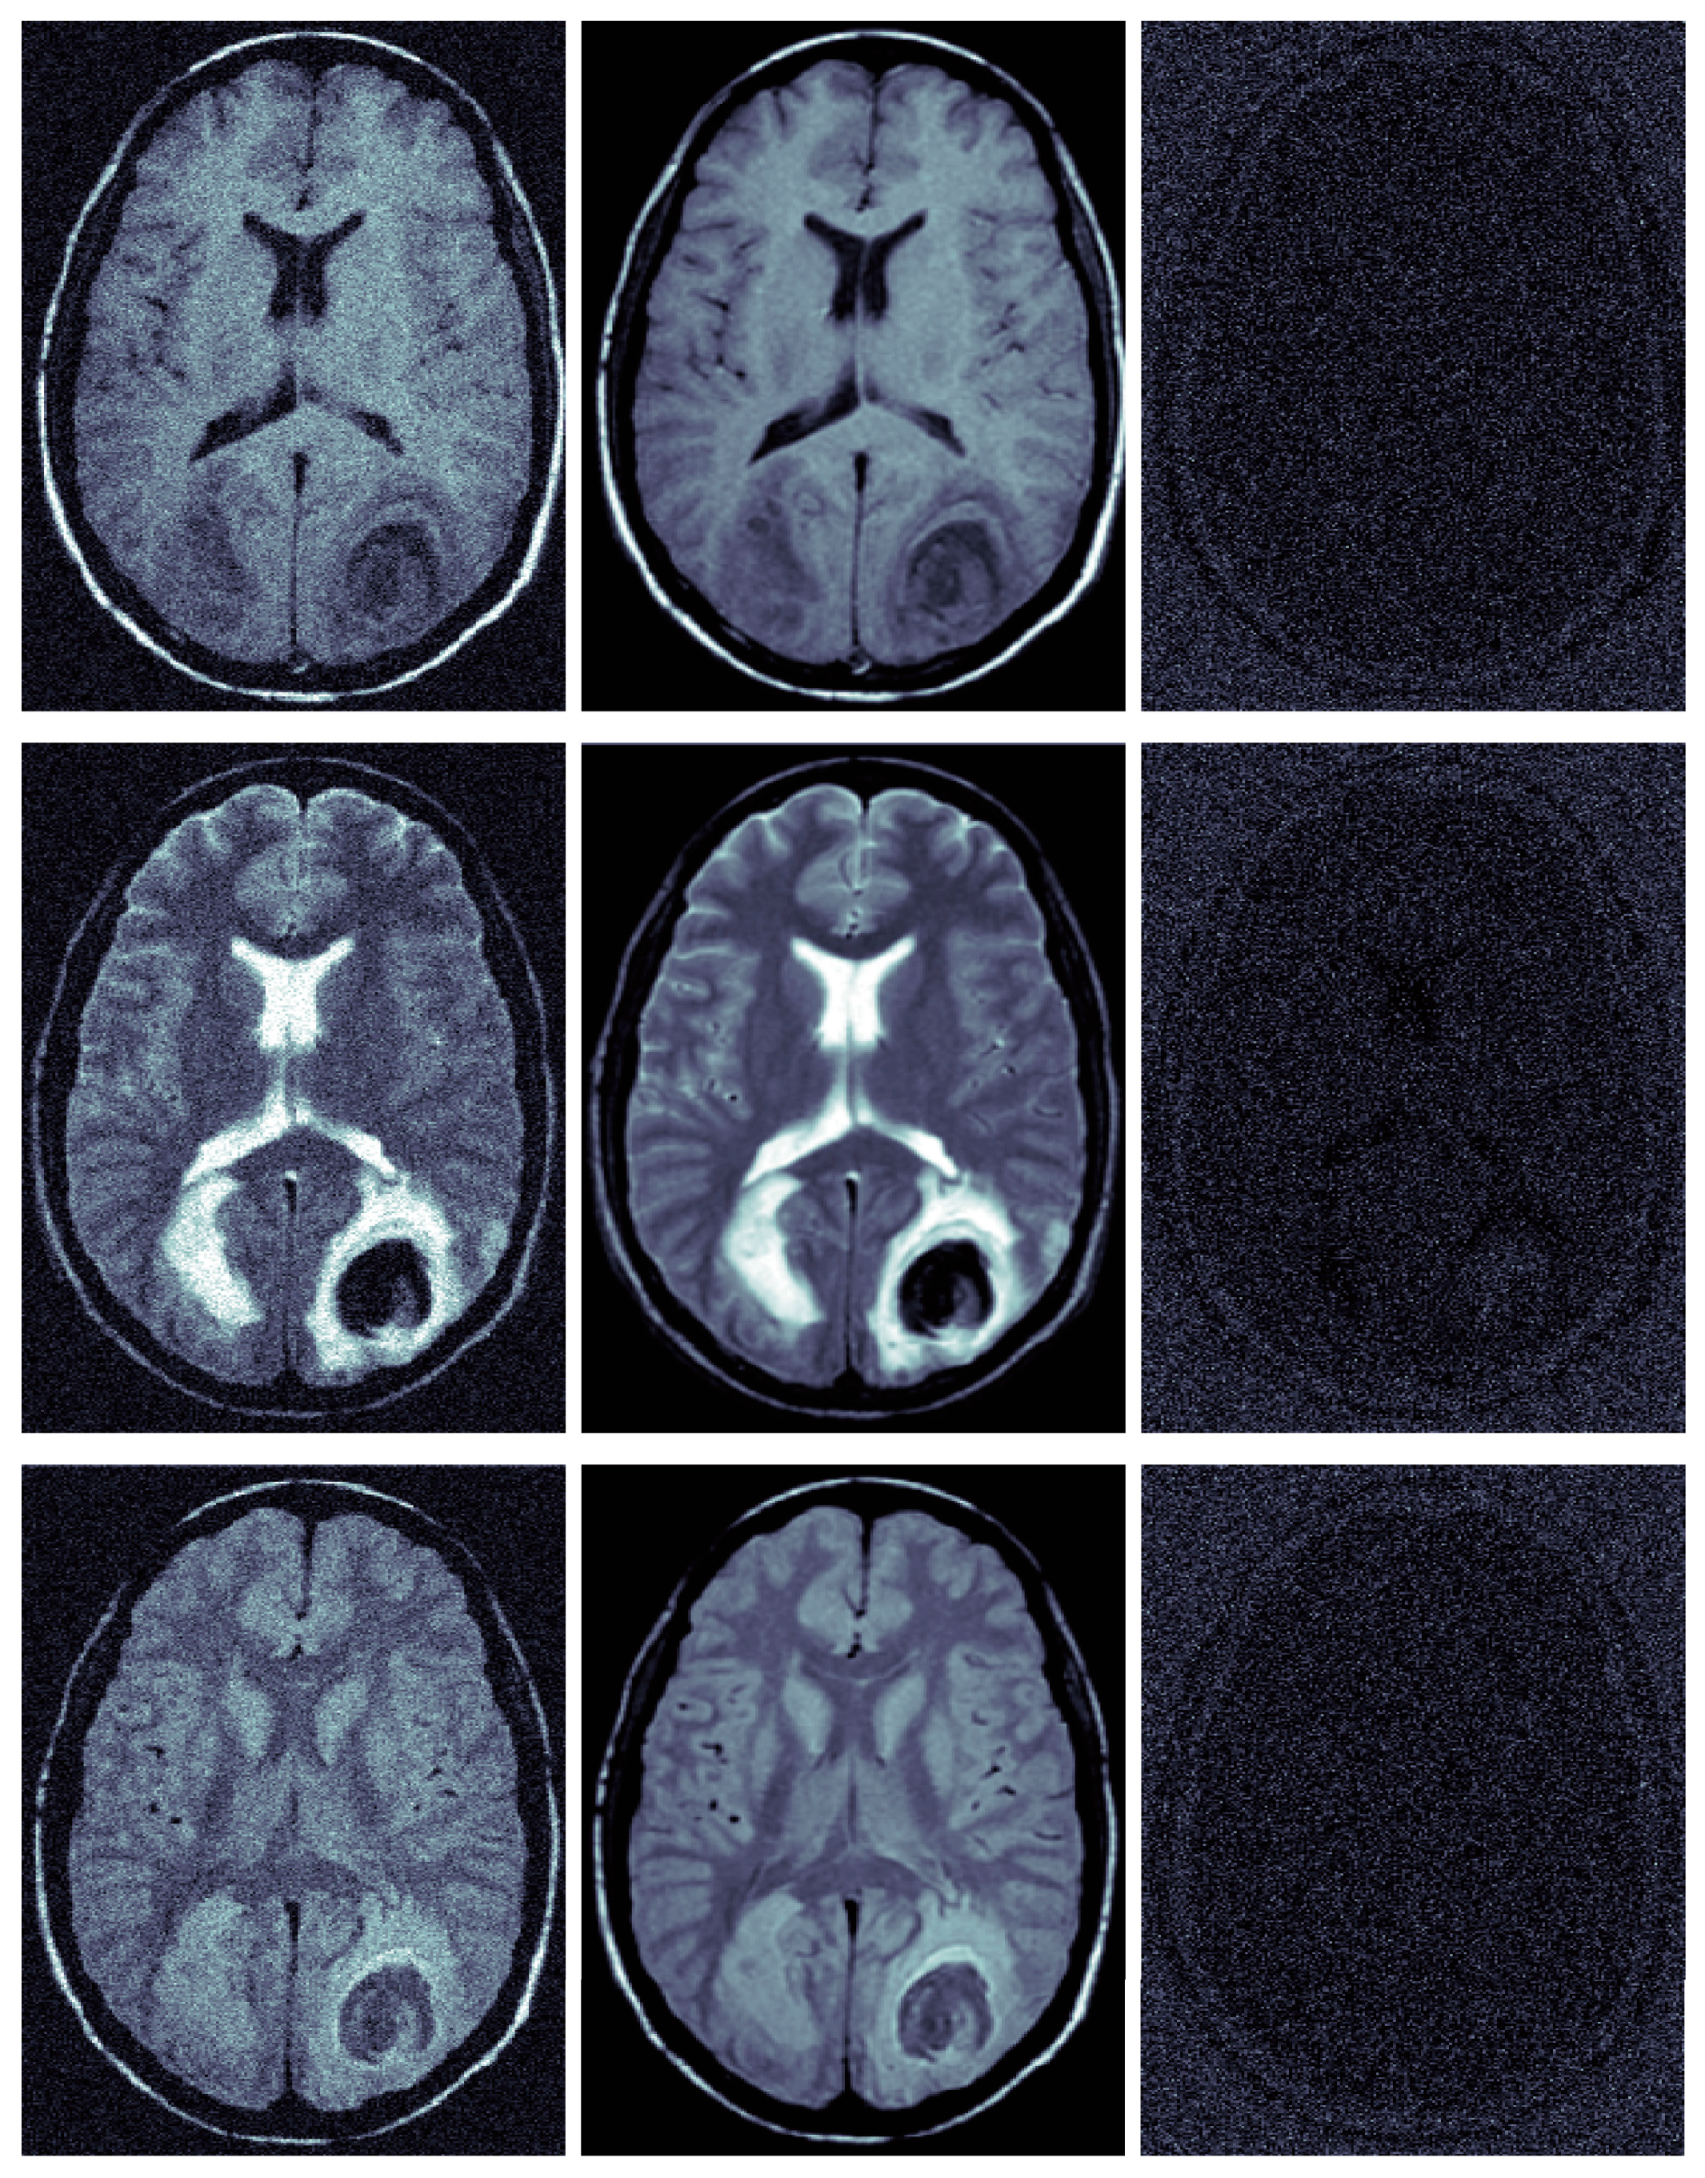

3.2. Evaluation of Real Clinical MRIs

3.3. Evaluation Focused on Diagnostic Tasks